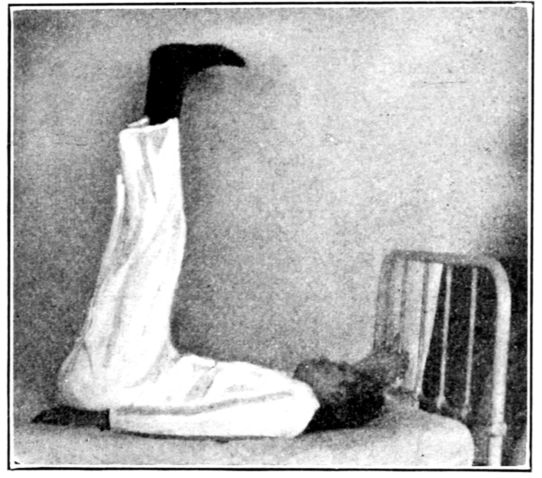

| 40. | Patient in right-angled position to relieve varicose veins | 138 |

| 41. | Elevated Sims position | 139 |